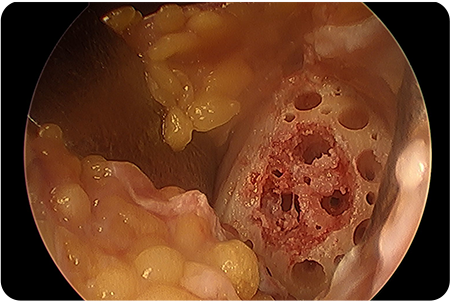

2. 관절내시경 검사 및 손상 부위 정리

닳거나 손상된 연골 조각을 제거하고, 치료할 부위를 깨끗하게 다듬습니다.